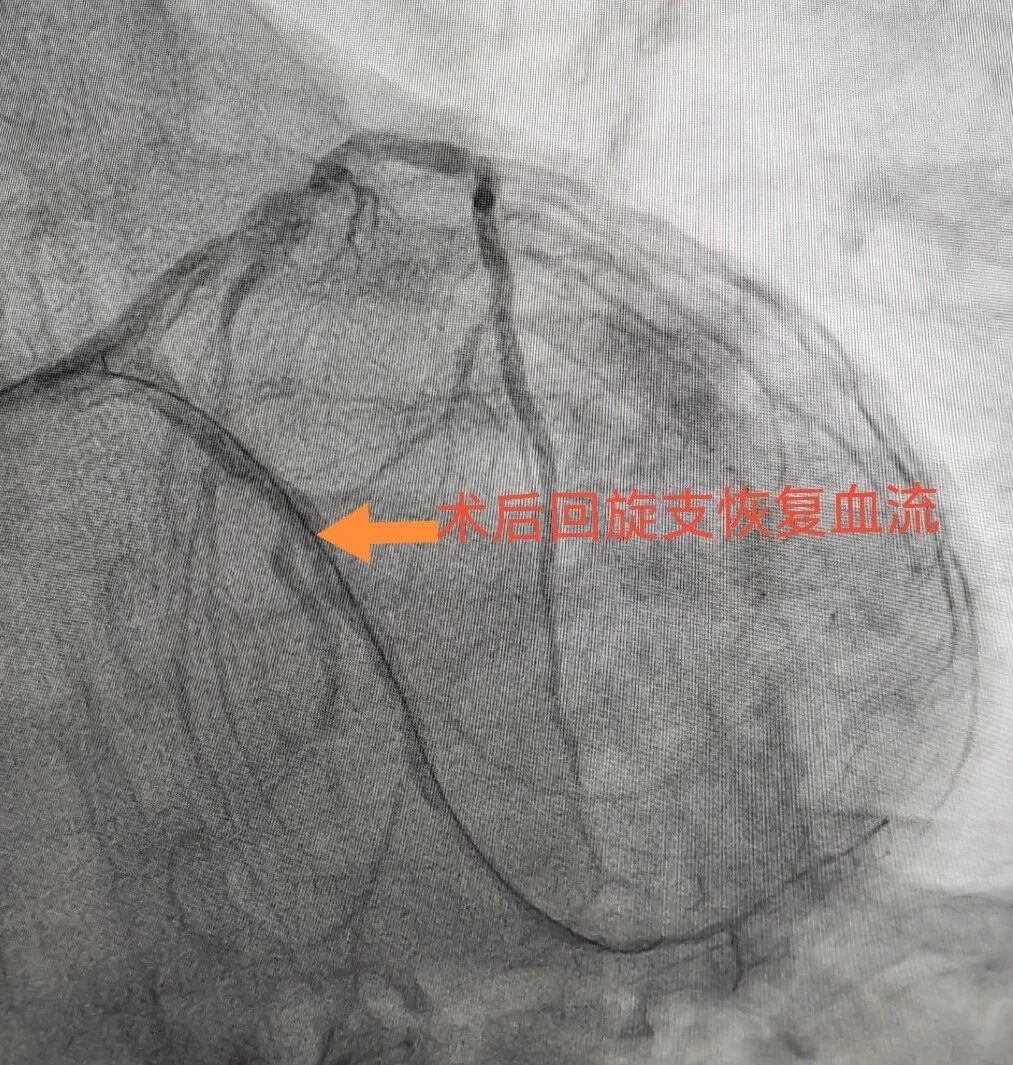

介入导管室的医生们都有一双“穿针引线的巧手”,他们凭借穿刺针、导管、导丝进行微创操作,疏通原本堵塞的血管,点燃患者生命之光。为了手术方便,介入医生们穿的铅衣大多设计成分体式,上半身是铅背心,下半身是铅围裙,而为了保证手臂的灵敏度,胳膊、手、脸、眼睛等部位仍然要裸露在外,并不能完全防止辐射。

北京中医医院内蒙古医院心病科现有北京常驻专家两名,科室为国家中医优势专科,自治区中医临床重点专科,自治区中医特色重点专科,市级中医重点专科,中国急性心肌梗死规范化救治项目内蒙古救治协作分中心,国家心血管病中心高血压专病医联体,国家标准化心脏康复中心建设单位。科室开展急诊冠脉介入,复杂冠脉介入,精准冠脉介入等技术。在冠心病,心功能不全,高血压,心律失常、糖尿病等方面充分发挥中西医结合优势,提高临床疗效,减少患者再住院率,提高患者生活质量,得到广大患者的好评。